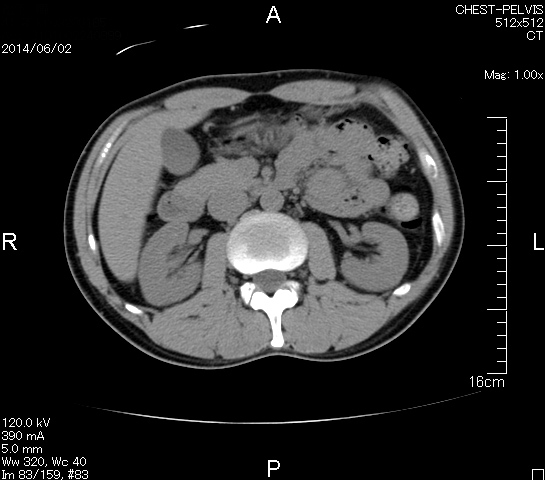

とうとうやってきた、この日が。

2006年入院治療の退院日から10年。 かなり大きな節目なんだが、なんだろうこの軽い感じは(笑)。 「10年生きたんだぁ」くらい。 変わったような変わっていないような。 当時は10年後なんて全く考えていなかった。 今も10年後は考えていないが・・・。 退院前日の2006/10/31は46.6kgだった。 今日計ったら54.8kg。体脂肪は16.6%。 とても健康にストレスなく生活できていることに、治療当時から現在に至るまで、関わった人全員に感謝の気持ちです。 マーカー、CT画像、問題なし!! 血液検査結果もほとんど文句なしの正常値。 そうだなぁ、数値に出ない異変としては、肩凝りかなぁ。 一旦夏になくなったと思ったが、初秋から再発。 マウスを左手にしたり、シップ貼ったり、最近はホッカイロ貼ったり。 で、一向に良くなる気配がない。 やはり四十肩なのか。 でも肩の可動域は問題ない。動かせないような痛みも無い。 結局色々考えてたどり着いたのは「変形性頚椎症」ではないかと。 肩凝りや頭痛がダラダラと続くようになるという症状がピッタリ当てはまる。 さて、改善策がなかなか難しい。 整形外科行ってもレントゲン撮って湿布をくれるだけだろう。 そんなことに大金を出すならまずは300円/回のプールで泳ごうと思う。 重力から開放して全身運動をするのが一番良いらしい。 2015年の目標は少しでも良いから水泳を再開する、だな。 マーカー、CT画像、問題なし!! 通常の血液検査結果も文句なしの正常値がズラ~っと並んだ!! 間違いなくヨメの食事のおかげである。ほんとうに感謝である!! ちなみに最近少々腰周りの肉付きが気になっていたのだが・・・。 左から2013年12月、2013年06月、2012年12月と背骨の位置は合わせて並べてみた。 6月まではあまり変化がなかったが、この半年で明らかに違う。 背中側の脂肪がやや増えてはいる。 でも最も大きな違いは、腸なのか、やたらと内臓が膨れている・・・。 一言で言うと食べすぎ?!?! 食事は野菜中心ではあるが、確かによく食べているw。 せっかくスーツのウエストを詰めたんだからこれ以上にならないようにしたい。 「腹八分目を心がける」かな。